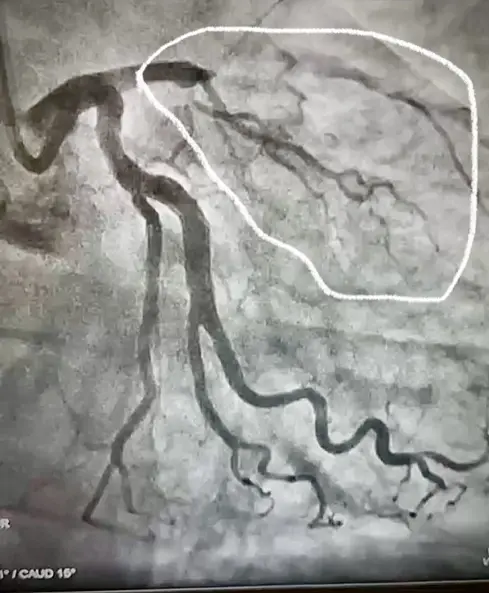

O jornalista José Roberto Burnier compartilhou em seu Instagram, nesta terça-feira (29), a imagem laboratorial de um exame do coração após ter sido vítima de um infarto durante o plantão de Ano-Novo na Rede Globo.

Exame de coração

Legenda: O jornalista compartilhou uma imagem do exame através das redes sociais

"Foi submetido a cateterismo cardíaco que detectou oclusão da coronária descendente anterior, sendo realizado angioplastia desta artéria com implante de stent", disse a equipe médica do Albert Einstein em comunicado.